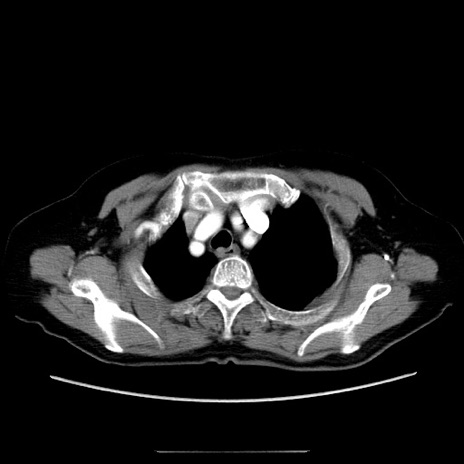

冠状断像

【症例】70歳代女性

【主訴】お腹が張る

【現病歴】1週間くらい前から腹部膨満の自覚あり。昨日夜から増悪したため、本日救急外来受診。

【身体所見】意識清明、BT 36.5℃、BP 165/106mmHg、HR 80bpm、SpO2 98%、腹部:膨満、軟、自発痛・圧痛なし、触診にて不快感あり、腸蠕動音:減弱

【データ】WBC 12600、CRP 1.04